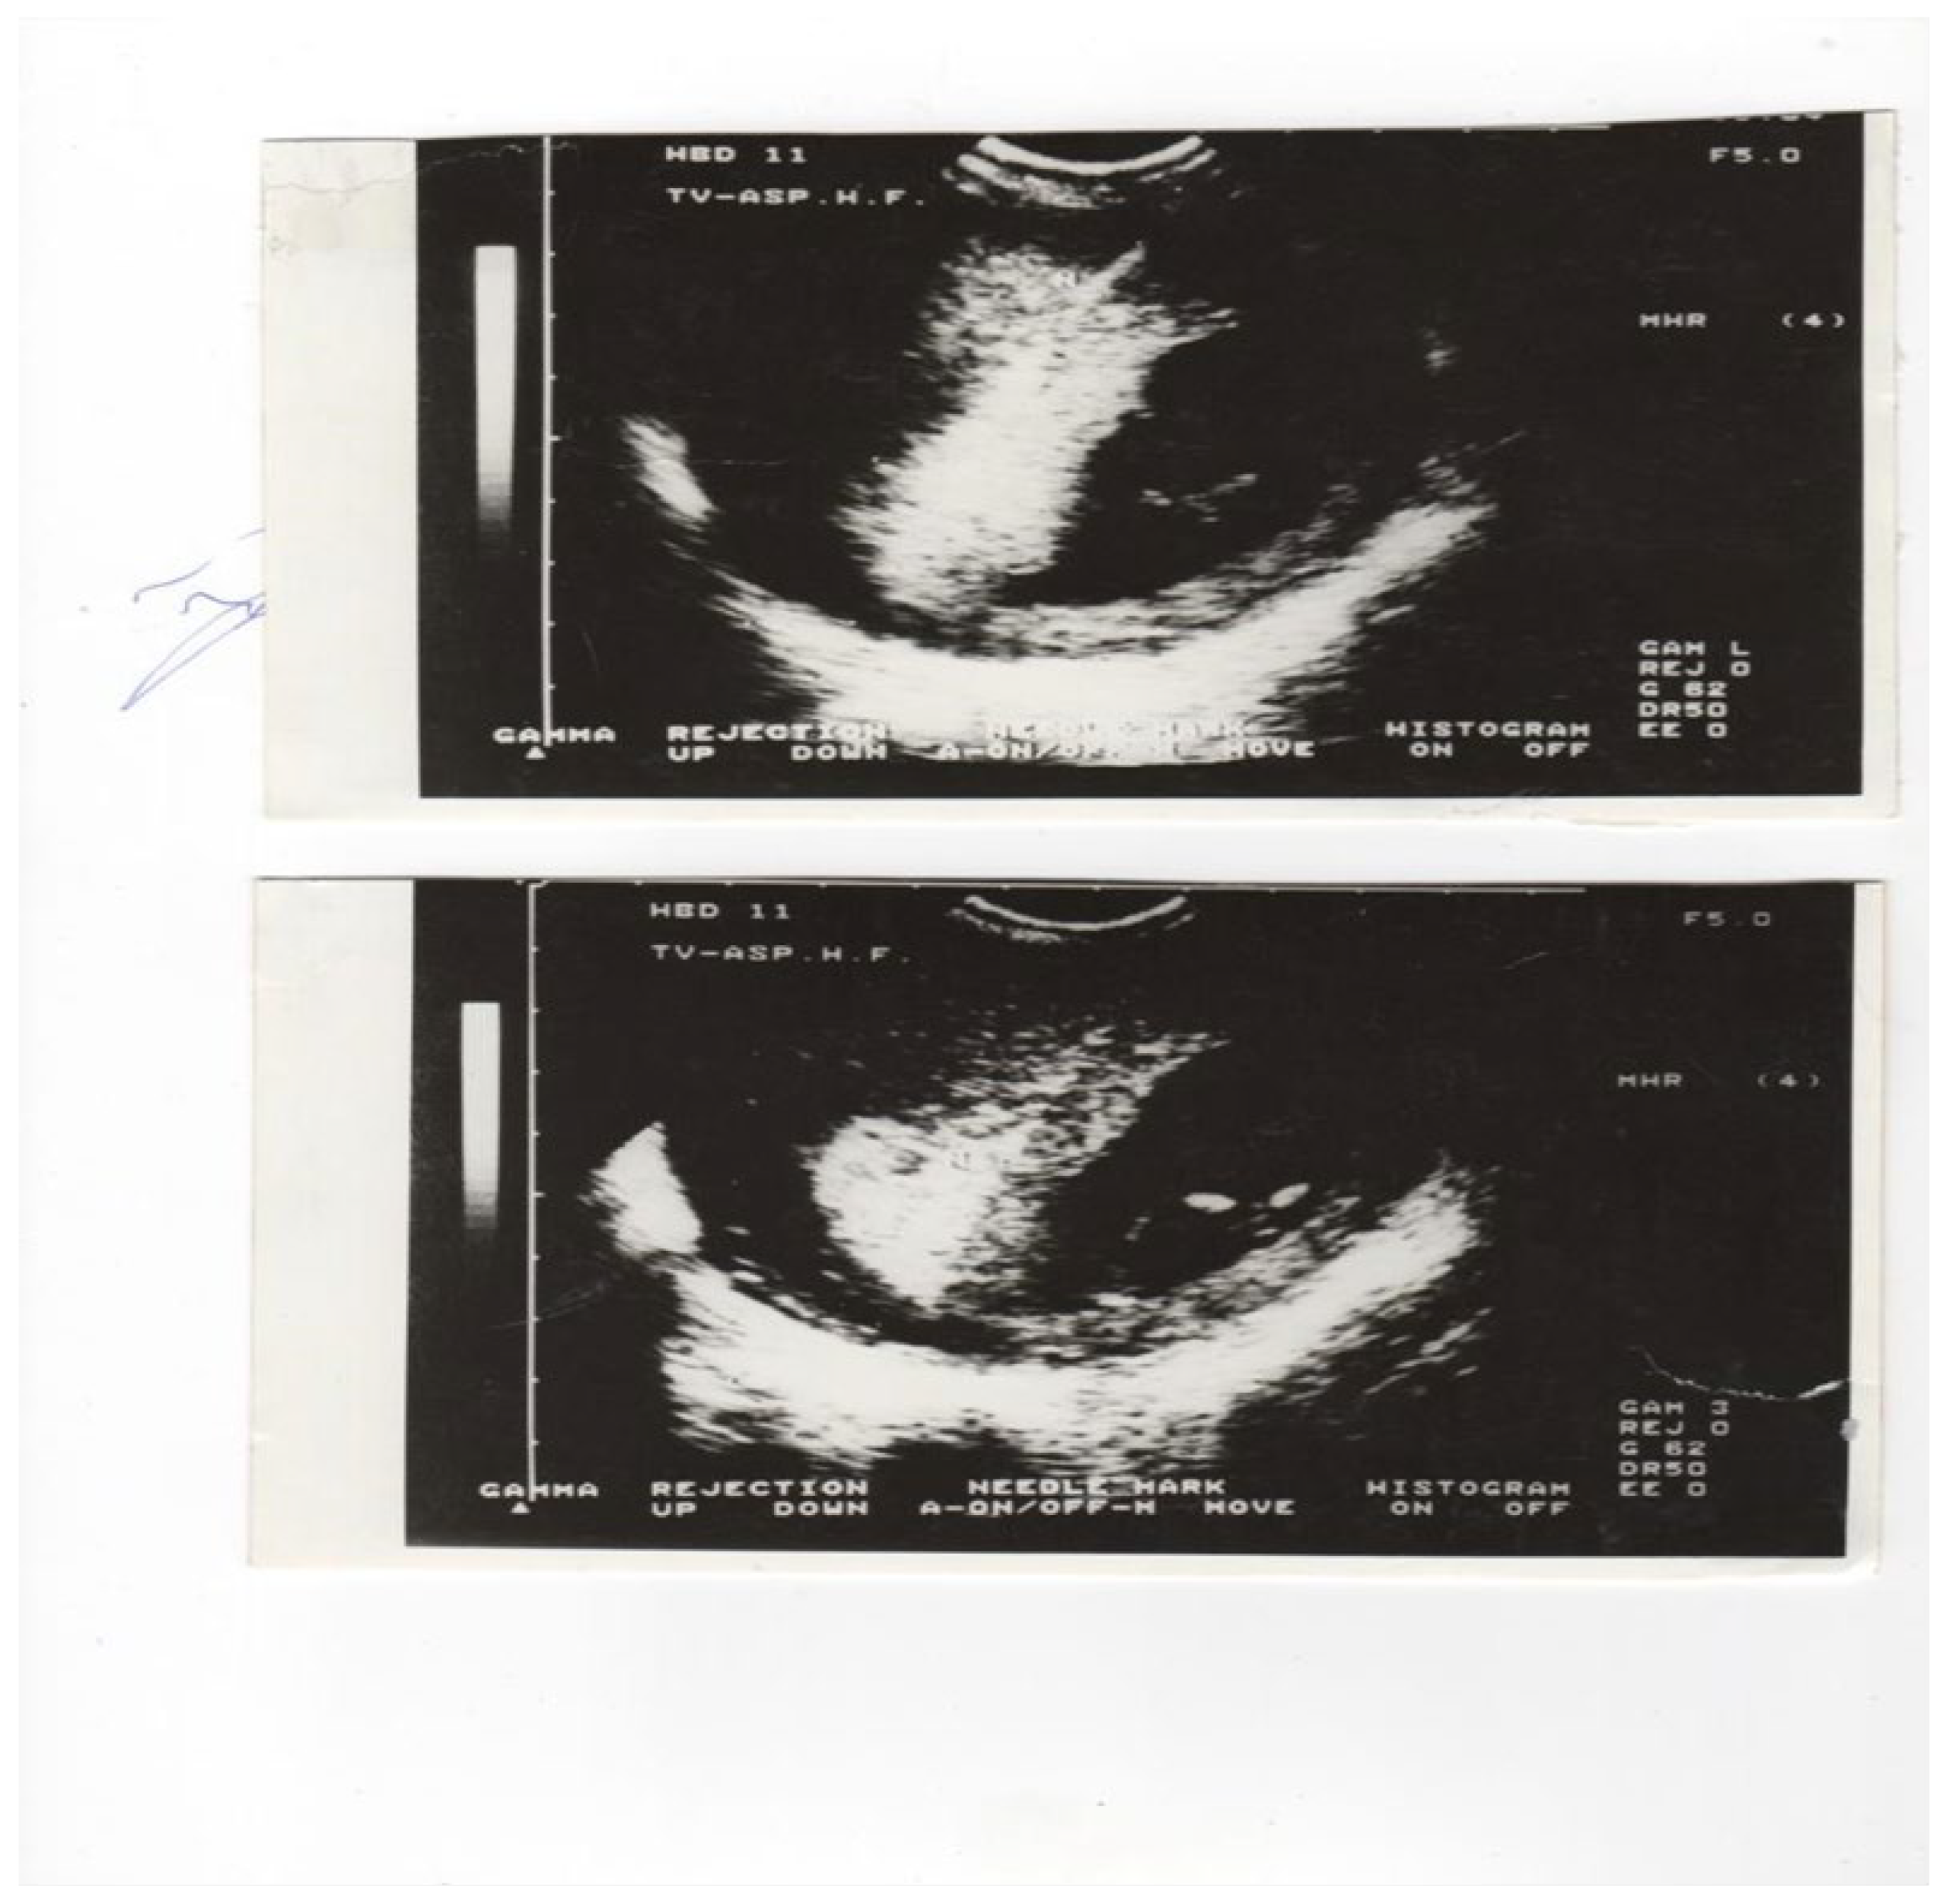

Cytogenetic findings [1,2,3,4,6,8,10,11,12,13,19,20,21,22,23,26] indicated that the sample of villus tissue was immediately transferred a laboratory and examined under a dissecting microscope (Figure 2.). An overnight short-term incubation method for three days or a culture method for seven days was used. Additionally, fetal heart rate (FHR) was monitored by M-mode in all patients. Fetal heart rates (FHR) were determined for each patient before and after CVS using the M-mode. In 200 patient’s alpha-feto-protein (AFP) levels were determined ten minutes before and ten minutes after CVS, to evaluate any feto-maternal hemorrhage.

Figure 2. Placental tissue under a dissecting microscope.